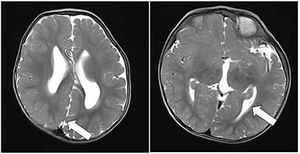

Case History: 15-month-old with focal seizure, developmental delay, disproportionate increase in size of head.